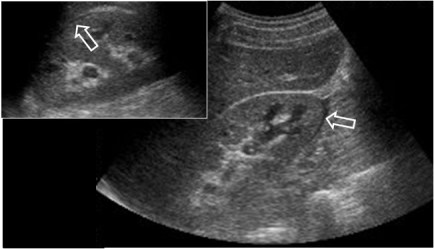

SIGNO DEL ESPAGUETI

Se trata de un defecto de repleción lineal en la vejiga, en pacientes con hematuria macroscópica. Corresponde a un coágulo cuya forma lineal indica que proviene del uréter, que hace de molde. El signo sirve para orientar la búsqueda del sangrado por encima de la vejiga. Aunque el Signo del espagueti se describió como una hallazgo de la urografía, también puede verse en otros métodos de imagen: cistografía, TC, ecografía y RM.